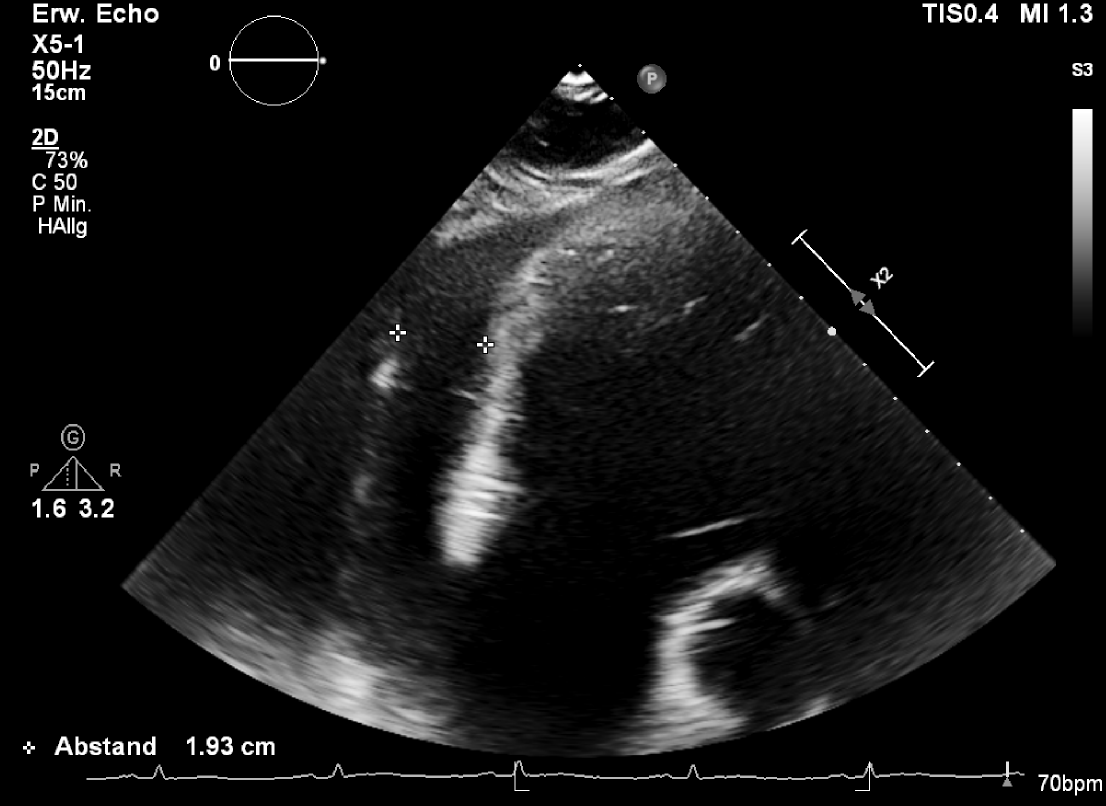

Case Presentation: A 22-year-old previously healthy male presented with cardiogenic shock and echocardiographically confirmed pericardial tamponade (Figure 1). Emergency pericardiocentesis drained 2.5 L of hemorrhagic fluid, and the patient was stabilized in the ICU with inotropic support. Transthoracic echocardiography revealed global left ventricular dysfunction (EF ~10%). Empiric antibiotic therapy was initiated. Cardiac MRI showed diffuse myocardial edema consistent with perimyocarditis, along with a large pericardial effusion. Endomyocardial biopsy revealed lymphocytic infiltration without eosinophils or giant cells. High-dose corticosteroids and chochizin were administered, leading to full recovery of left ventricular function. Extensive infectious workup remained negative. However, repeat cardiac MRI revealed a contrast-enhancing mediastinal mass with infiltrative growth into the right atrium and ascending aorta as well as relapse pericardial efusion. PET-CT demonstrated intense FDG uptake in the lesion, raising suspicion for malignancy (Figure 2).Subsequent targeted CT guided biopsy confirmed the diagnosis of a high-grade, undifferentiated angiosarcoma originating in the mediastinum with direct cardiac invasion. The patient was transferred to an oncology center for further management and systemic therapy planning.

Figure 1: Transthoracic echocardiogram showing a large (1.9cm) pericardial effusion surrounding the heart.